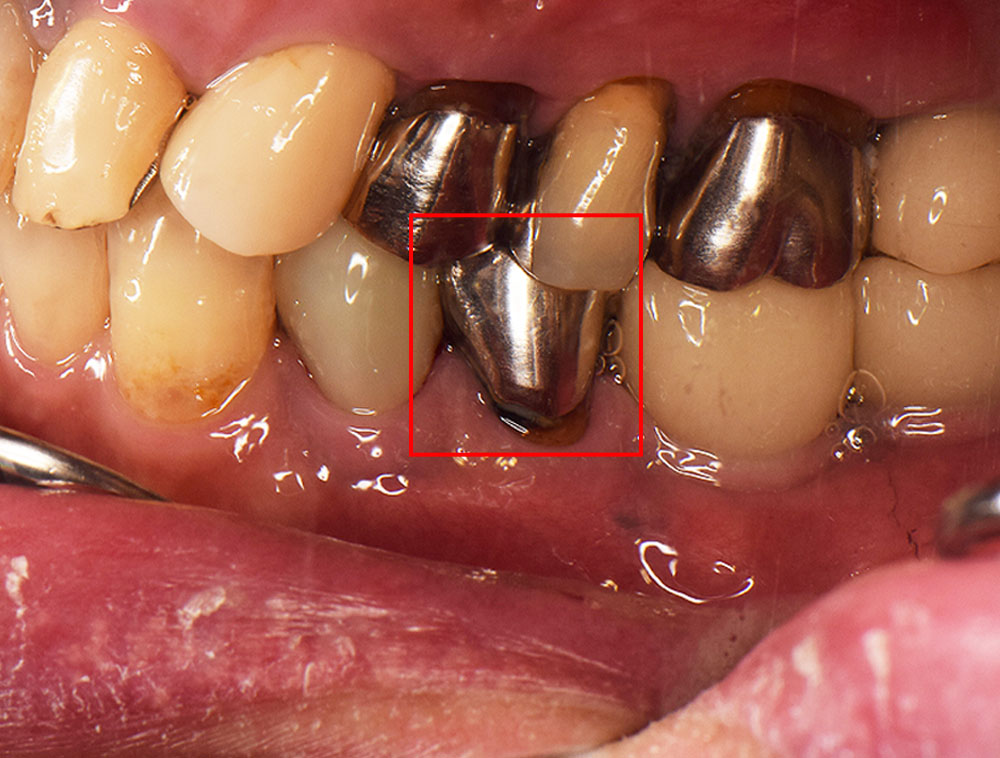

歯周再生治療前

歯周再生治療後

患者さんは40代の女性で、歯がグラグラで噛めないので噛めるようしたいと恵比寿・広尾歯科に来院されました。お口のなかを拝見すると歯周病が進行し特に奥歯の歯周ポケットが深くなり、歯を支える顎の骨が溶けている状況でした。歯ブラシで磨きにくいため汚れが溜まりやすいだけでなく、奥歯は噛み合わせの力が強く加わり歯周病の悪化しやすい歯です。この患者さんも以前、保険の銀歯で治療されていましたが、年々歯がグラグラ(動揺)して噛めないとご来院されました。

歯周病認定医でもある院長 前島による歯周病診断、歯周基本治療のうえで、エナメルマトリクス蛋白(EMD/エムドゲイン)による歯周病再生療法により失われた顎の歯を支える骨を再生します。このエナメルマトリクス蛋白は、幼若ブタの歯胚から抽出・精製したもので、このタンパク質により歯が生えるメカニズムを応用して失われた骨の再生を促します。今回は基本歯周治療と歯周再生療法による歯周病治療をおこないました。